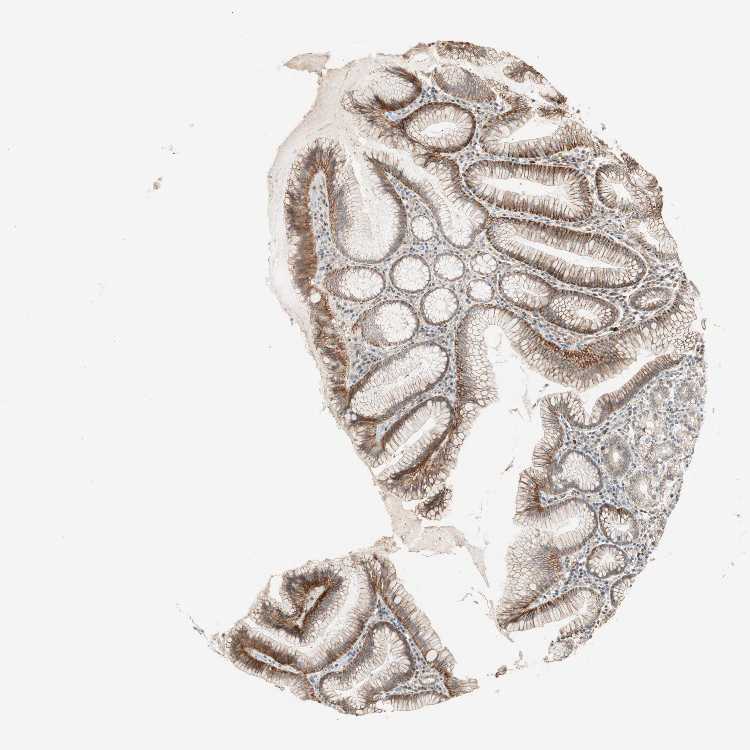

STOMACH 1 - Antibody stainingi

Antibody staining in the annotated cell types in the current human tissue is reported as not detected, low, medium, or high, based on conventional immunohistochemistry profiling in selected tissues. This score is based on the combination of the staining intensity and fraction of stained cells.

Each image is clickable and will lead to virtual microscopy that enables deeper exploration of all samples and also displays staining intensity scores, fraction scores and subcellular localization as well as patient and tissue information for each sample.

Antibody HPA003750

Glandular cells High